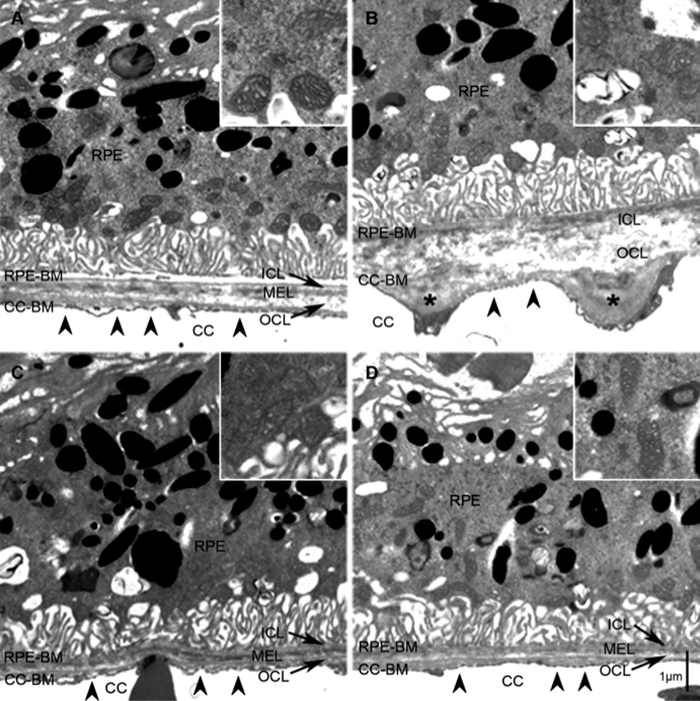

Inhibition Of The Alternative pathway Of Complement Accelerates Recovery From Smoke-Induced Functional And Morphological Ocular Injury

The Alternative Complement Pathway Deficiency Amerliorates Chronic Smoked-Induced Functional And Morphological Ocular Injury

The Alternative Complement Pathway Mediates Functional And Morphological Deficits In A Smoke Model Of Age-Related Macular Degeneration